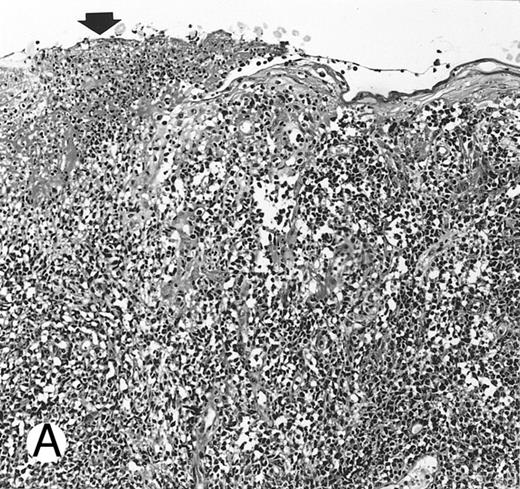

Fig. 1.

Nasal-type NK/T-cell lymphoma presenting as nodular skin lesion (case no. 28). (A) The skin shows focal necrosis of the epidermis and ulceration (arrow). (B) The lymphoid infiltrate in the dermis shows angiocentricity, as evidenced of the higher density of cells in the expanded walls of the blood vessels (arrows).

Histologically, the lymphomatous infiltrate was diffuse or patchy, with angiocentric and angiodestructive growth being observed in 30 cases (88.2%) (Figs 1 and 2). The cytologic composition was variable from case to case, including predominance of small cells, medium-sized cells, or large cells, or a mixture of these cell types (Fig 2 and 3). The tumor cell nuclei frequently showed irregular foldings and granular chromatin (Fig 2B). The larger cells possessed distinct nucleoli. The cytoplasm was moderate in amount and often pale. Karyorrhexis was usually prominent. Zonal tumor cell death, focal or confluent, was evident in 27 cases. In the 14 cases for which Giemsa-stained touch preparations were available, azurophilic granules could be identified in at least some of the neoplastic cells.